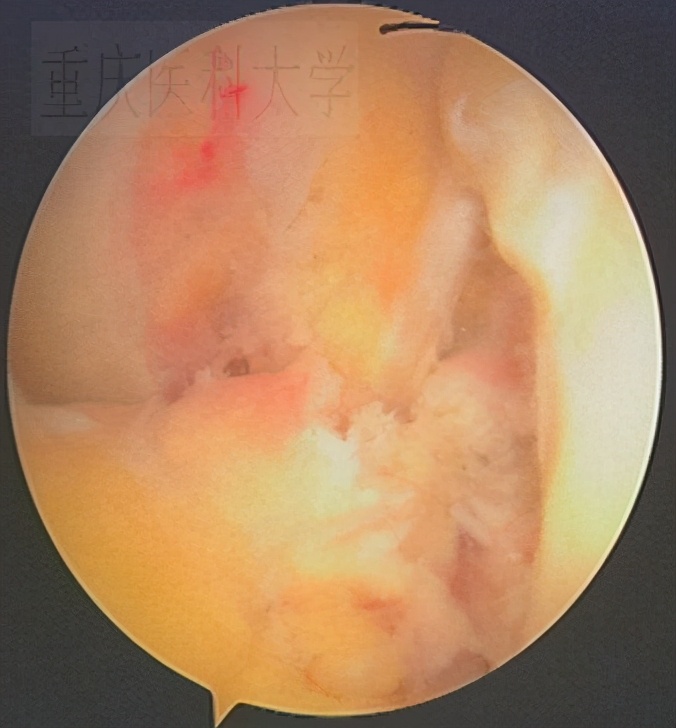

重建术前的 前交叉韧带 :

重建术前的 前后 交叉韧带损伤